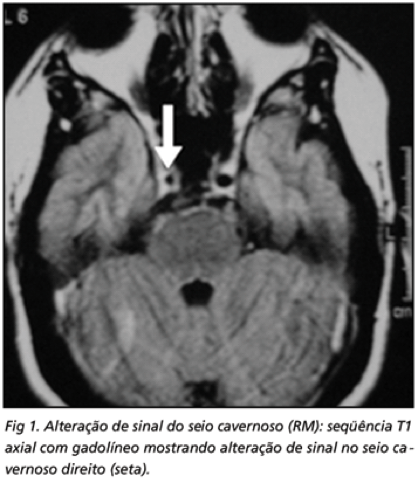

SÍND. DE TOLOSA-HUNT

RNM de crânio com contraste:

Alterações inflamatórias do seio cavernoso

Alterações inflamatórias na fissura orbitária superior ou vértice da órbita

Estreitamento focal da artéria carótida interna

TC de crânio pode demonstrar lesões semelhantes, porém é menos sensível

Achados similares são vistos em linfoma, sarcoidose e meningioma